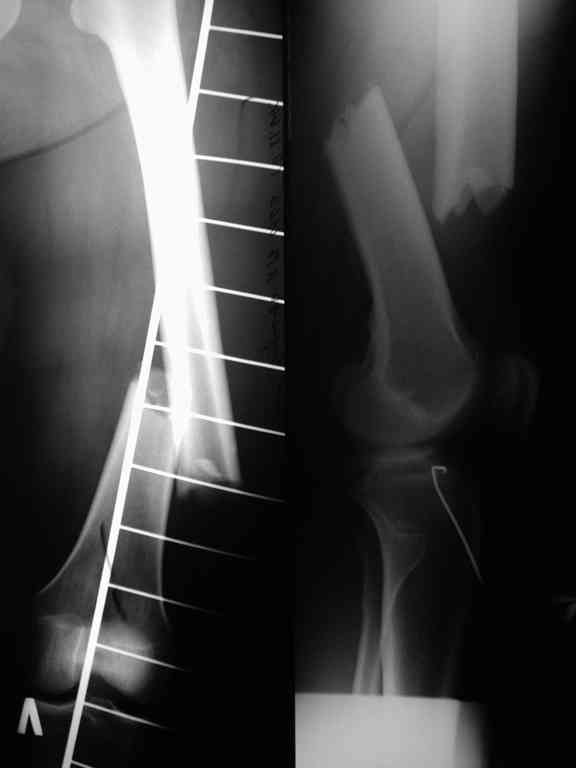

Соматически здорова. В ноябре 2004 года падение с высоты 12 м, перелом правой вертлужной впадины со смещением, неврит седалищного нерва, откр. перелом дистального отдела большеберцовой кости справа и закрытый перелом с/н/3 левого бедра. К нам поступила через 3 недели после травмы, был выполнен в 2 сессии сначала интрамедуллярный ретроградный остеосинтез бедра слева, затем остеосинтез вертлужной впадины и голеностопа справа. При остеосинтезе бедра пришлось немного приоткрыться в зоне перелома для репозиции и вообще операция затянулась часа на 2.5-3 (это один из наших первых интрамедуллярных синтезов). Через 4 месяца при нагрузке весом около 50 кг постепенно развилась варусная деформация бедра с искривлением стержня. Закрыто выпрямили под наркозом, динамизация гвоздя,но в сентябре 2005 г. согнулось бедро снова. Гвоздь удалили, остеосинтез пластиной, декортикация, пластика спонгиозой из метафиза б/берцовой кости. Динамика заживления вялая, но конструкция стояла неплохо (без признаков расшатывания), постепенно дали нагрузку - в марте 2006 года - перелом пластины - реостеосинтез пластиной, пластика гребнем подвздошной кости. На контролях (за август, т.е. 4 мес. после операции - прилагаю) динамика положительная, разрешена нагрузка до 50 кг. В начале этой недели без падения вновь появились боли в бедре - на Р-граммах - перелом пластины (снимки прилагаю). Фоном ко всему этому то, что и перелом вертлужки и дистального отдела б/б кости тоже не срастаются, хотя на голени уже дважды выполнялась костная пластика, на впадине - вторичное смещение, перелом части металлоконструкций. Исследовали гормональный фон - парат-гормон и прочие щитовидные в норме, месячные регулярно.Прошу совета по тактике дальнейшего лечения и выяснения причины тотального несращения всего сломанного.

Уважаемый Александр. Случай достаточно интересный, поскольку за 2 года,почему то ничего не срастается и все ломается. Жаль нет рентгенограмм таза и голени.Основными причинами несращения переломов бывает 1.не правильно выбранная тактика лечения, в том числе тактика оперативного лечения ( к примеру - не тот фиксатор, не того размера, неправильно установлен и т.д.)2.Девитализация костных отломков, а судя по рентгенограммам старались вы на совесть, когда открывали область перелома при интрамедуллярном остеосинтезе. Кстати, если это был не блокируемый остеосинтез, а обычный, то понятно почему стержень согнулся и нет сращения. На представленных рентгенограммах отдельные винты расположены даже с внутренней стороны, т.е. открылись вы качественно. 3.не правильно выбранная тактика лечения в п.операционном периоде или не выполнения больным данных рекомендаций. По бедру - мы бы убрали пластину и выполнили ретроградный блокируемый остеосинтез с рассверливанием. Если нет возможности, есть аппарат Илизарова. Но мороки и для вас и для больного много.

В приложении рентгенограмма бедра за авгутст 2005 с согнутым гвоздем и первичные.

Отсутствие сращения косвенно говорит об этом. Хотя, судя по снимкам со стержнем, вероятны и другие проблемы. Раз есть диастаз - надо динамизировать стержень практически сразу, недели в 2-4 после остеосинтеза, а раз уж сращения в динамике не выявляется, зачем было с динамизацией ждать больше 2 мес.?